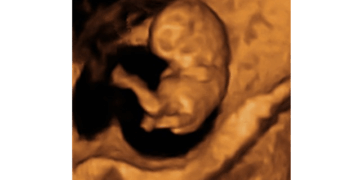

Should children have the right to keep living from the moment they’re conceived? The Colorado Secretary of State office so dislikes this question that they barred it from appearing on the 2026 ballot in Colorado for voters to decide. They…